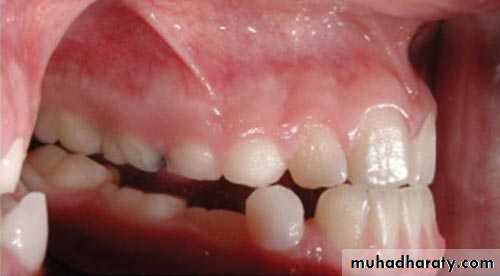

Radiograph showing impacted maxillary canines. Right canine is located labially while left canine is located palatally

Clinical photograph of the labial area where the right canine is localized labially